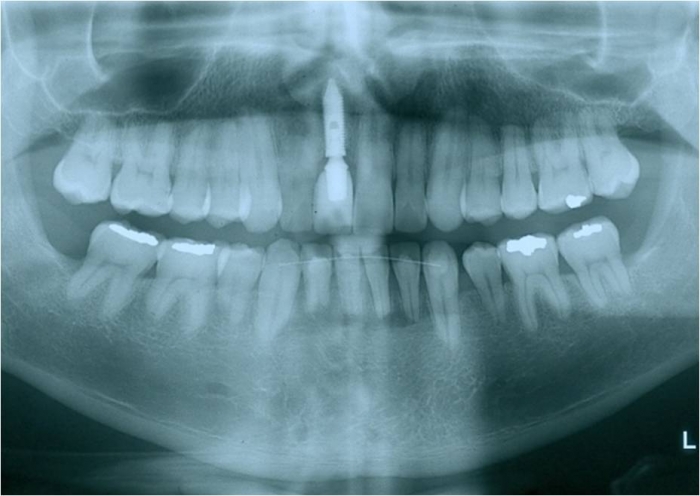

Rx com prótese fixa em porcelana